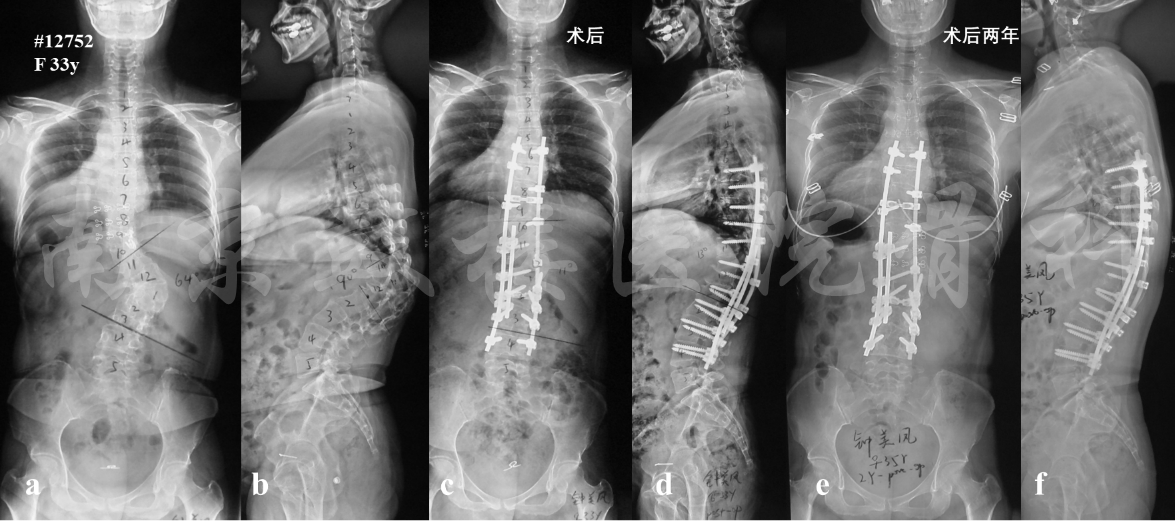

图5 女性,33岁,成人先天性脊柱侧后凸畸形。X片示T12楔形变,胸腰段角状侧后凸畸形(a, b),行T12全脊椎切除术(T12 VCR),并于截骨区使用卫星棒加固(c, d),术后两年无内固定失败或矫正丢失(e, f)